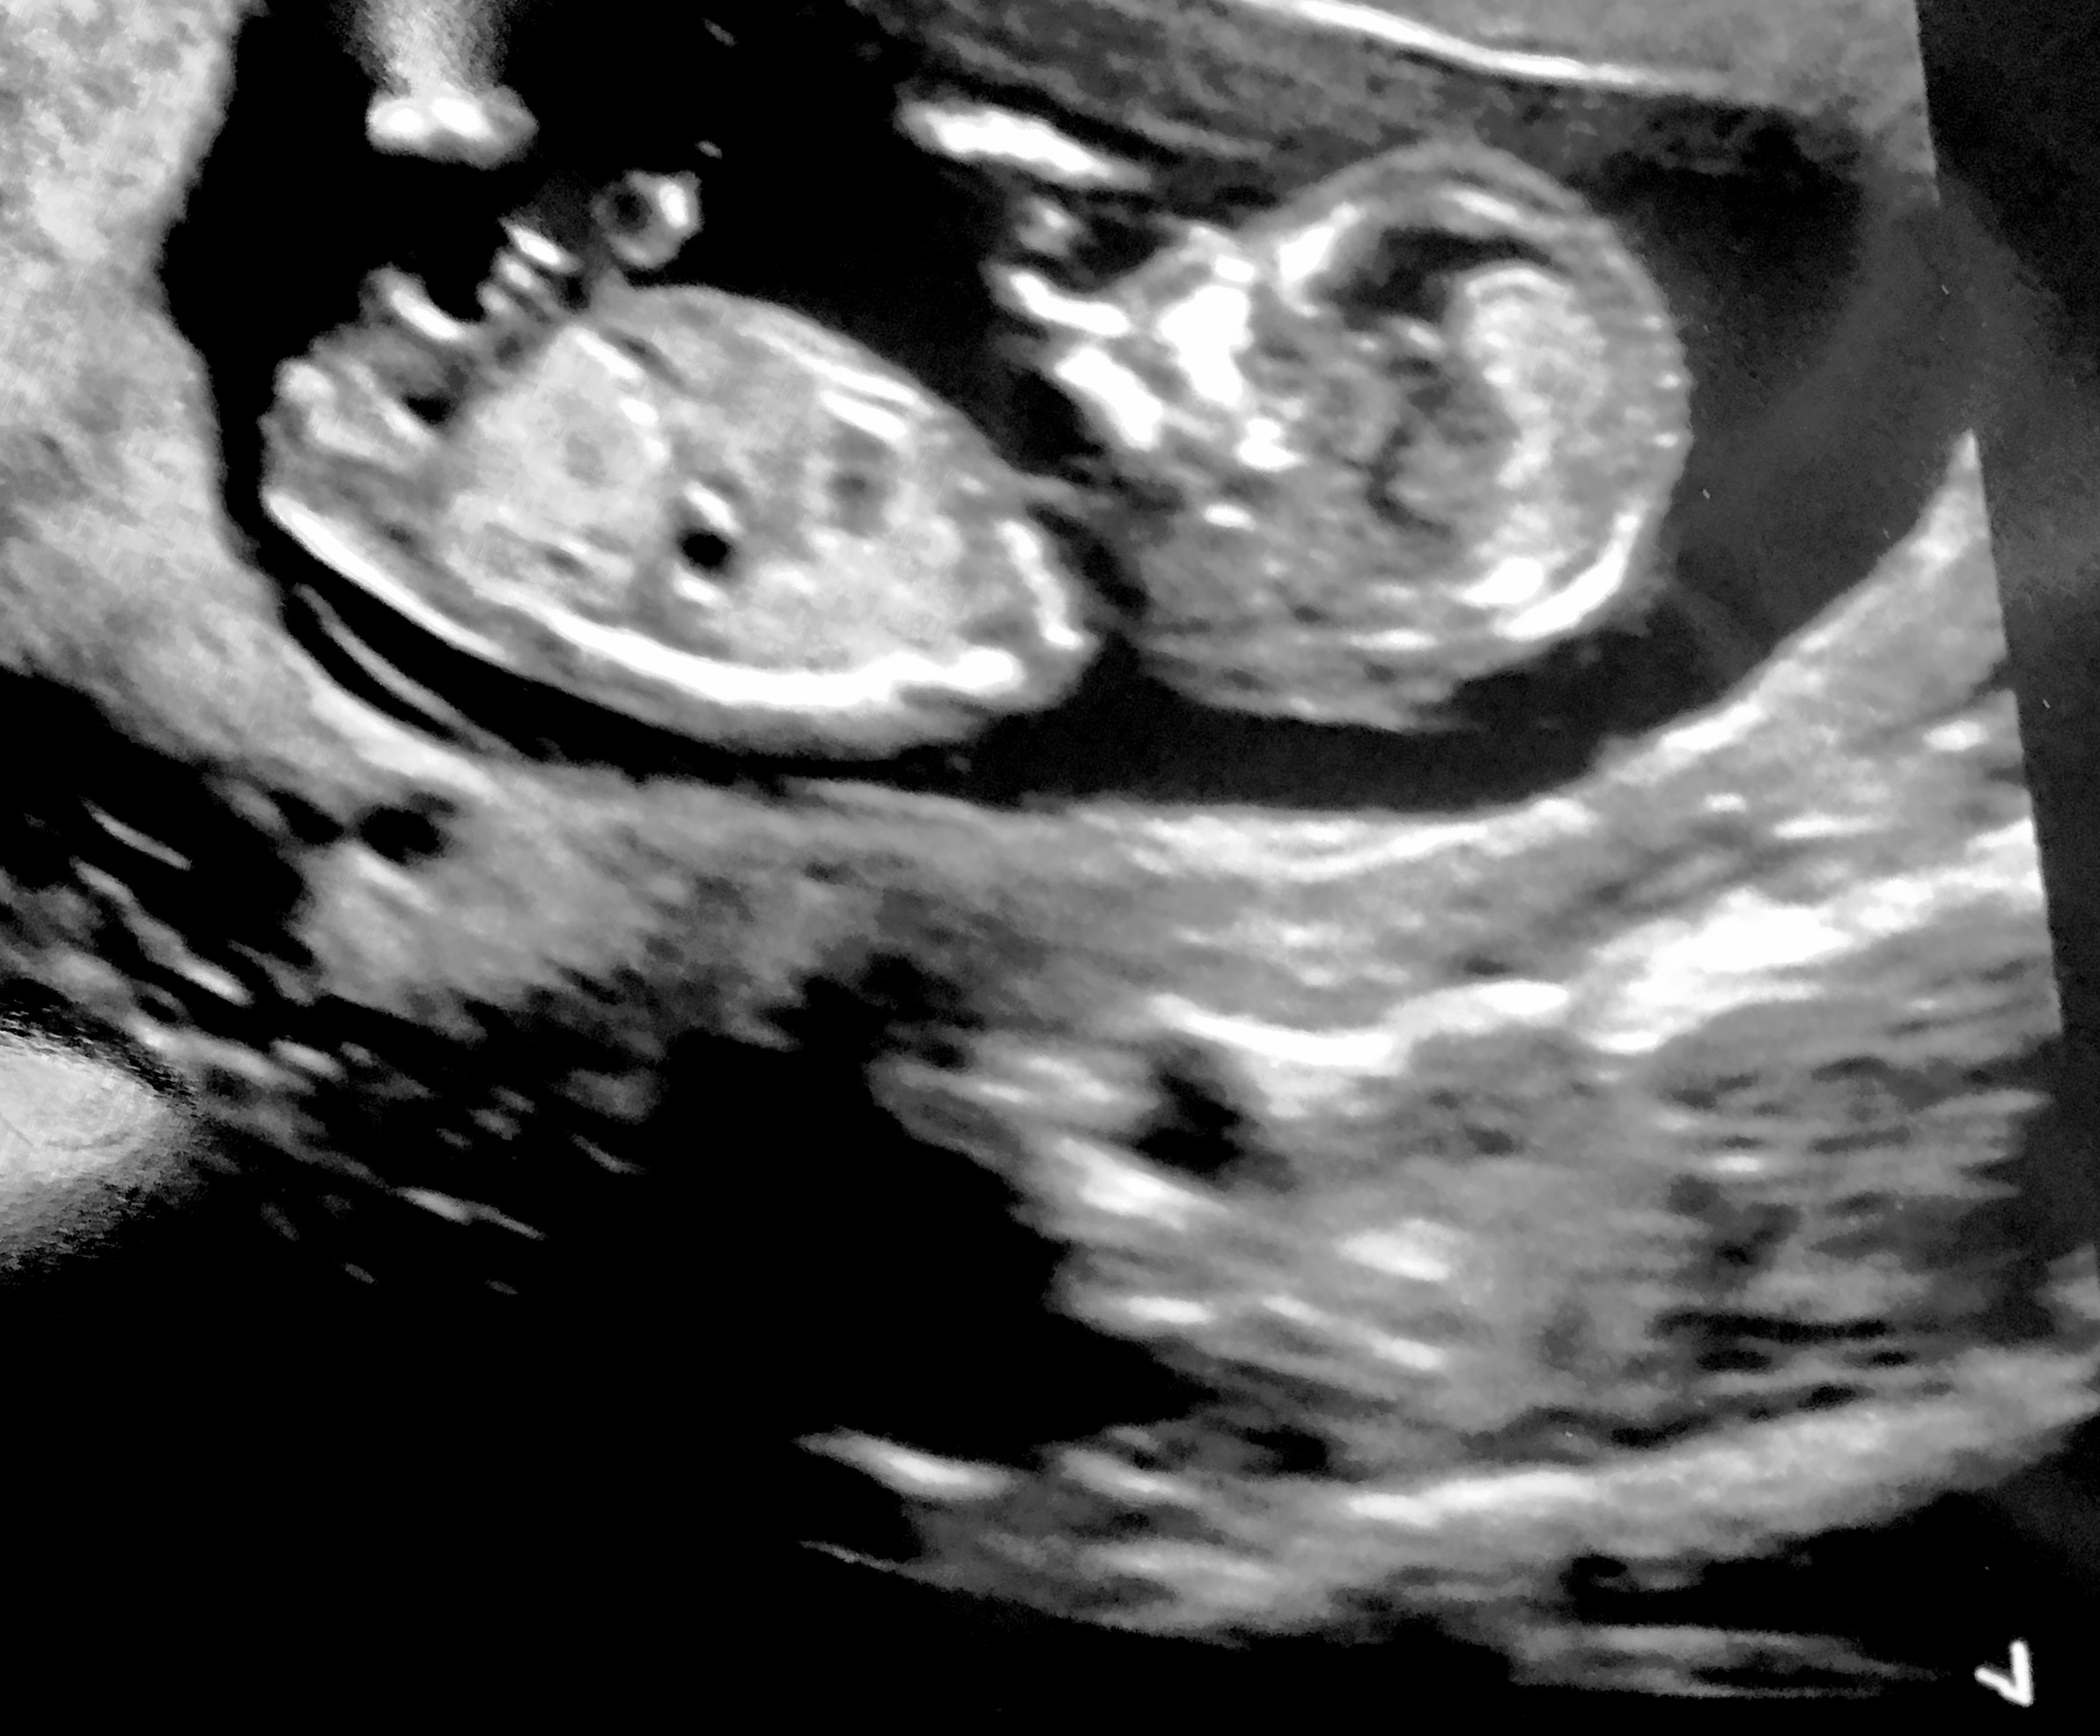

Attachment 34736 What do you all think please xx

I am guessing that is a boy nub.

Boy Sent from my SM-G955U using Tapatalk